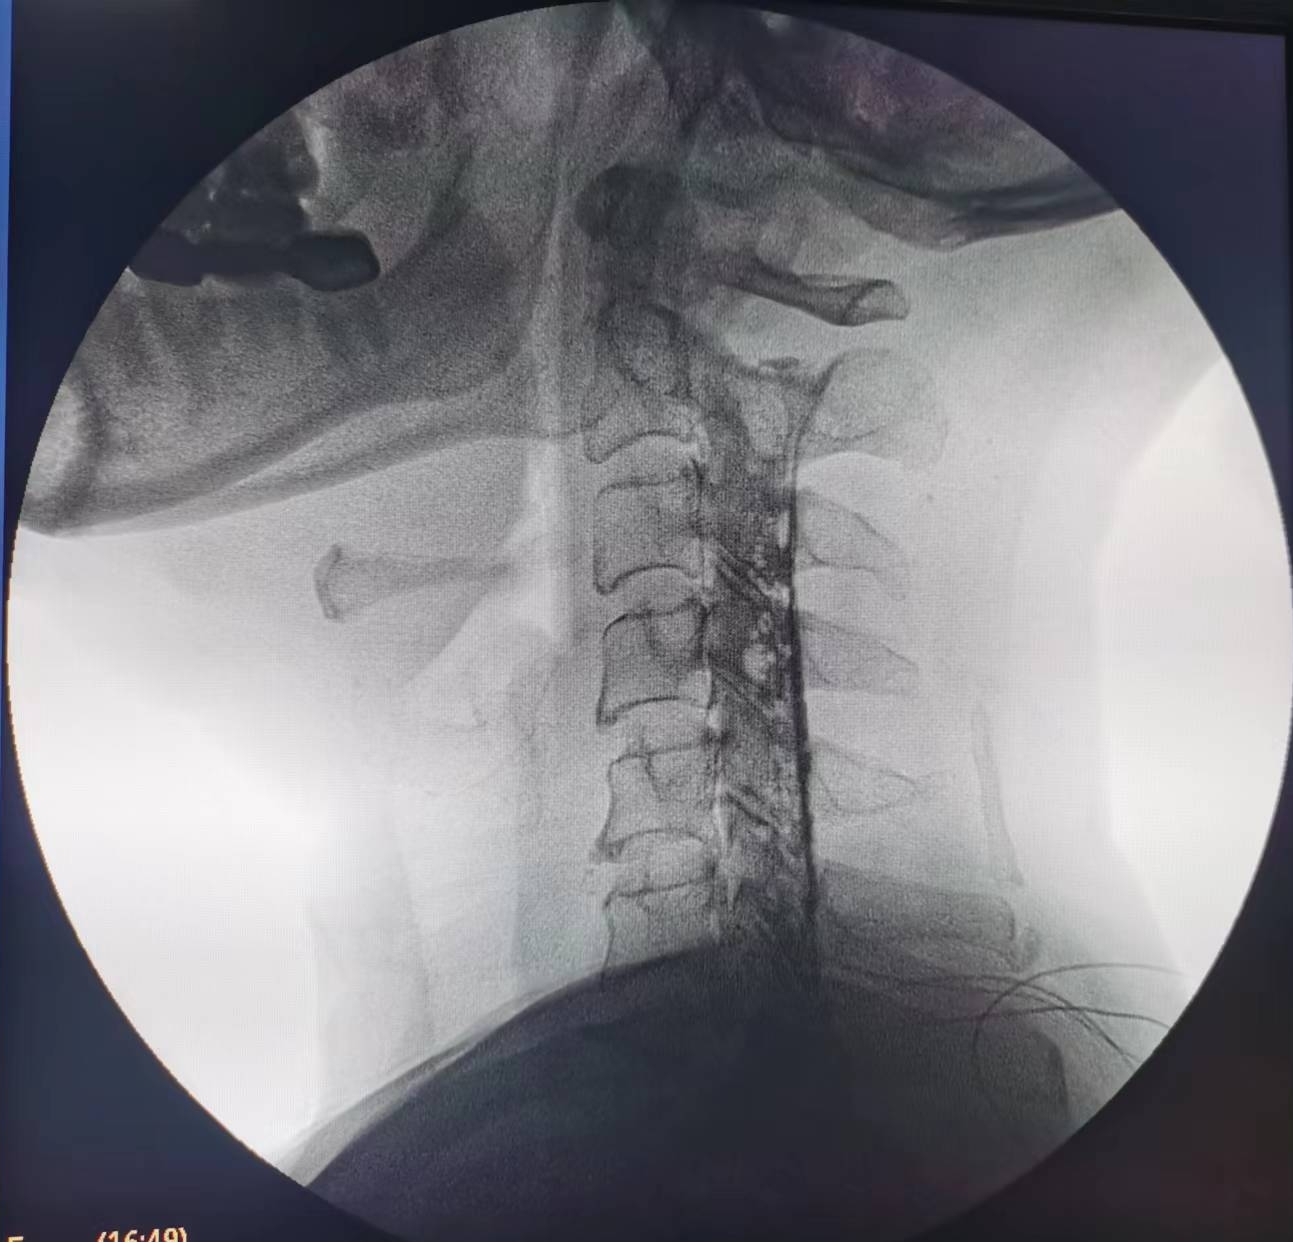

輾轉(zhuǎn)來到瀘州市中醫(yī)醫(yī)院疼痛科治療。由于疼痛嚴(yán)重,外加嚴(yán)重缺乏睡眠,黃大伯入院時焦慮、精神狀態(tài)很差??粗鼻邢虢獬纯嗟难凵?,疼痛科醫(yī)生團(tuán)隊抓緊時間完善診查,發(fā)現(xiàn)黃大伯病情為第6、7節(jié)頸椎間盤突出重,壓迫左側(cè)第7頸神經(jīng)根導(dǎo)致??紤]他年齡較大,團(tuán)隊決定給他做一種微創(chuàng)手術(shù)——膠原酶化學(xué)溶解術(shù):通過一支細(xì)小的針穿刺到突出的椎間盤,注射膠原酶,將突出的椎間盤溶解掉,以減除神經(jīng)的壓迫。

手術(shù)之后3天,黃大伯疼痛得到很好緩解,露出了許久沒有的笑容,終于可以安心躺著睡覺了,1個月后基本恢復(fù)了正常生活,6個月后復(fù)查CT發(fā)現(xiàn)突出的頸椎間盤已經(jīng)基本消失了,黃大伯一家人對治療效果非常滿意。

手術(shù)之前CT,巨大突出物 術(shù)后6個月復(fù)查CT:突出物消失